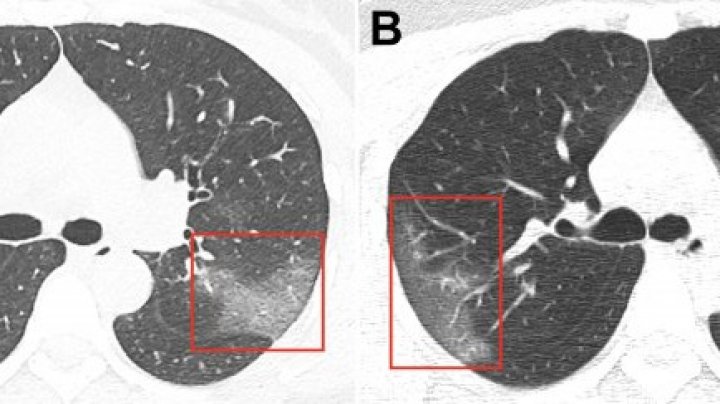

Chinese doctors have published CT Imaging of the 2019 Novel Coronavirus on journal Radiology.

A 33-year-old woman presented to the hospital with a 5-day history of fever and cough of unknown cause. She indicated that she worked in Wuhan, China (the center of novel coronavirus outbreak) but had traveled to Lanzhou, China, 6 days before presentation to the hospital.

After a series of investigations, doctors diagnosed her with 2019-nCoV pneumonia. After receiving 3 days of treatment, combined with interferon inhalation, the patient was clinically worse with progressive pulmonary opacities found at repeat chest CT.